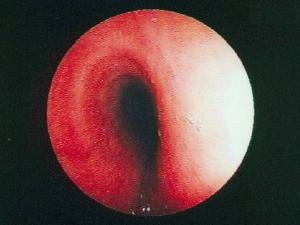

Broncofibroscopia

Observe el edema, eritema y congestión de la mucosa traqueal, la estreches de su luz, por la disminución de su diámetro transverso debido a la compresion extrinseca por la lesion mediastinal, la pared mucosa posterior, esofágica de la traquea con aspecto de un canal por la procidencia de los extremos de los anillos traqueales en la luz endotraqueal. Esto impide progresar el endoscopio sin deterioro evidente de la pared traqueal y provocar una asfixia mecanica.